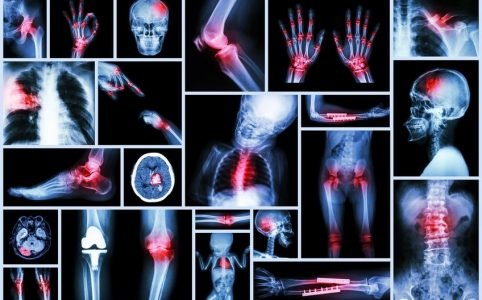

Sehnenverkürzungen: Ursachen, Verlauf, Diagnose Therapie

Sehnenverkürzungen können grundsätzlich an allen Gelenken im Körper vorkommen. Besonders häufig sind sie jedoch an den Fingern, den Füßen und Fußzehen und den Ellenbogen-, Knie- und Hüftgelenken.